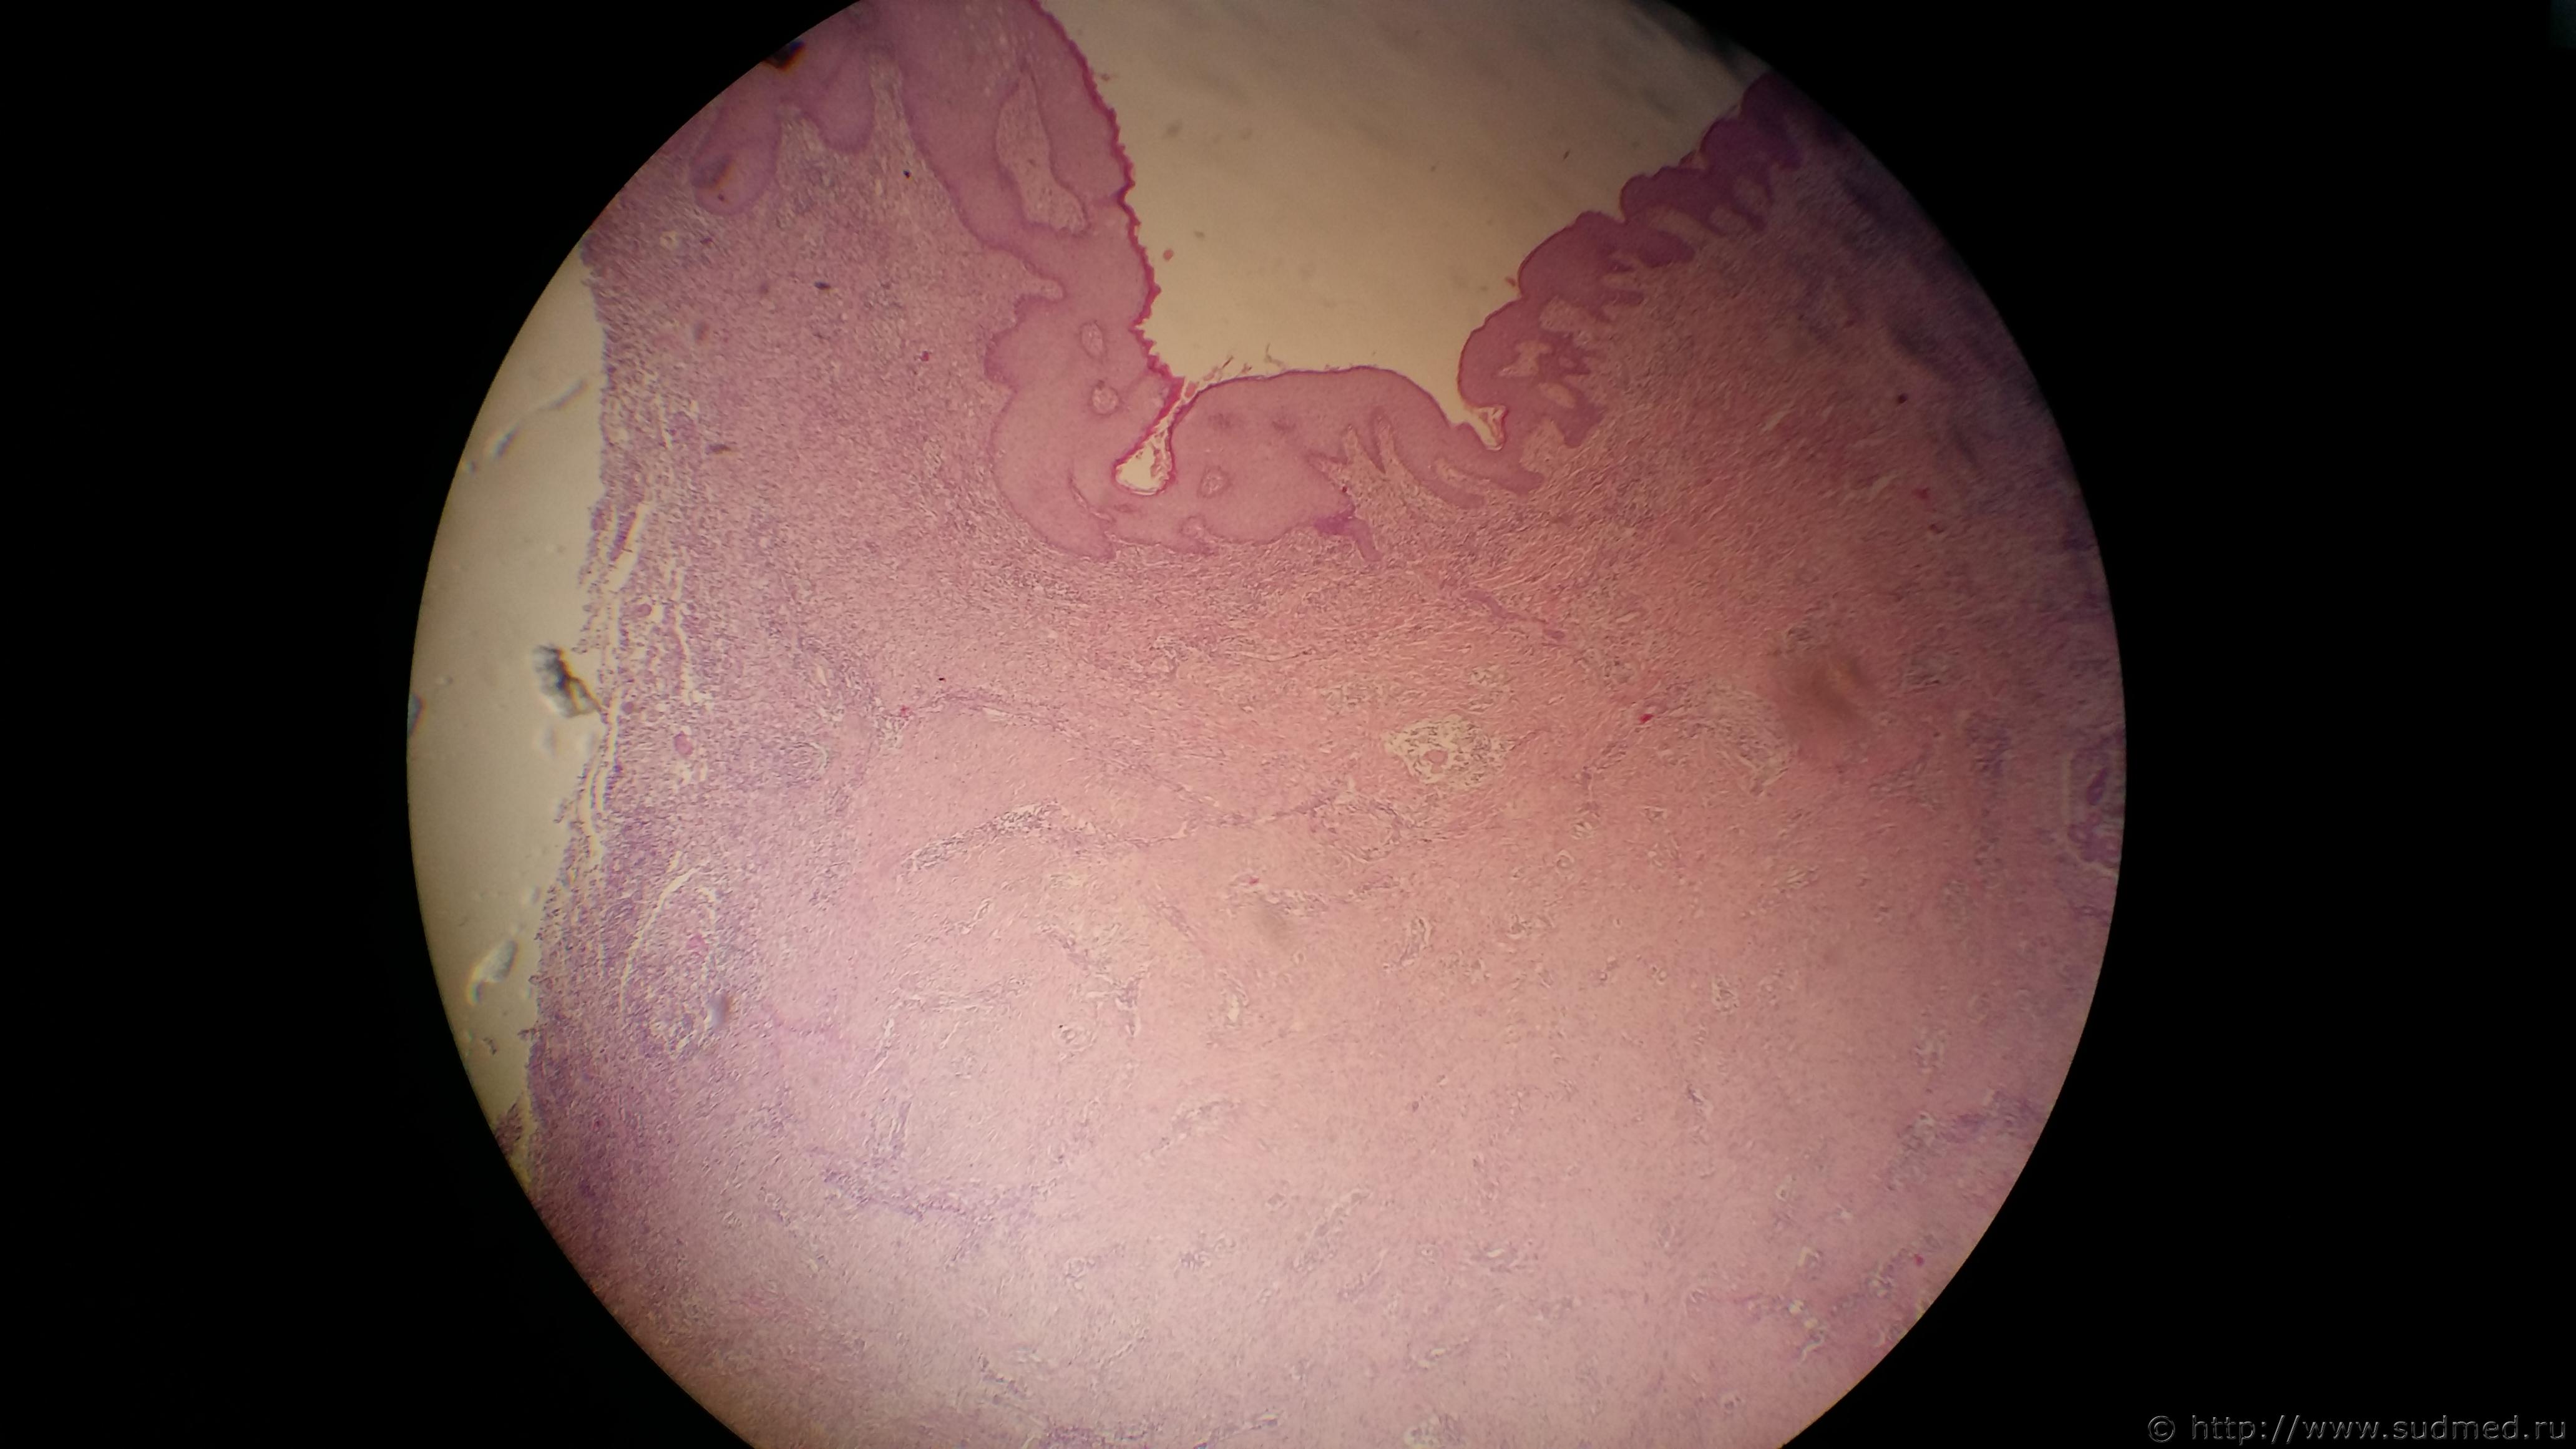

Женщина 30 лет. Карциноид-туморлет в легких